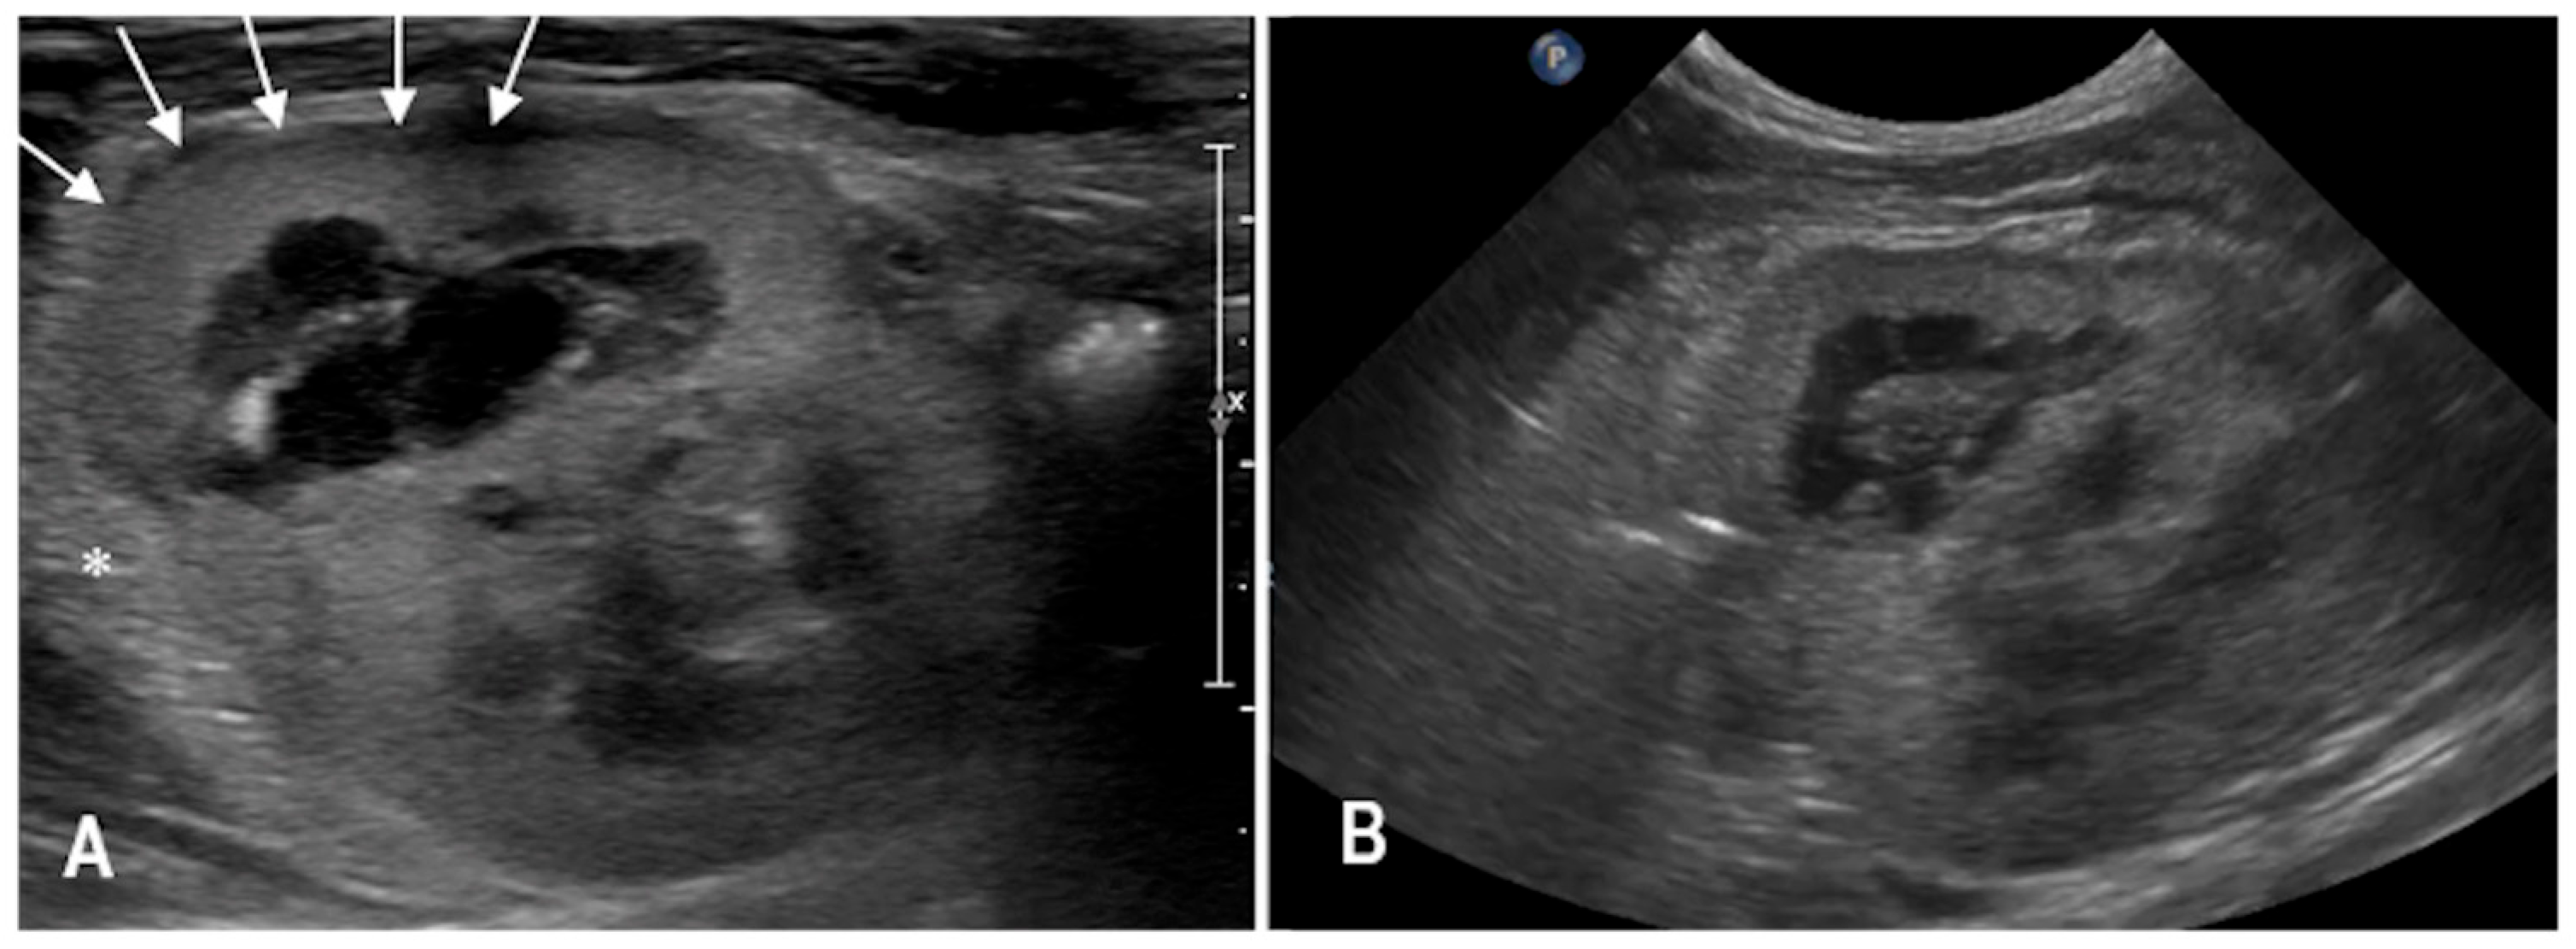

3.2. Case 2